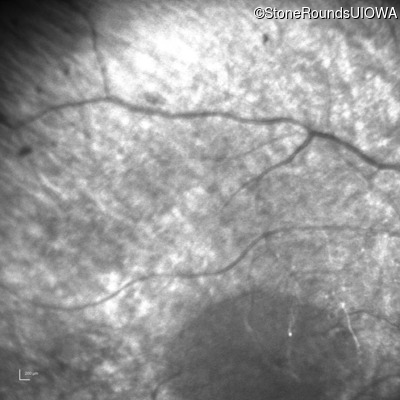

Infrared Fundus Photograph - Left - No Light Perception

Exemplar